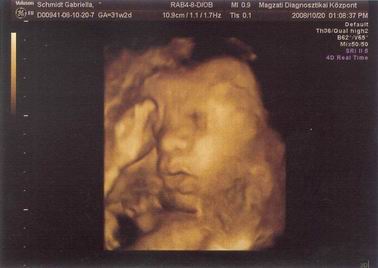

Kicsikristóf a 32. hét elején (vagyis épp egy hete).

BPD: 86 mm

HC: 313 mm

AC: 305 mm

FL: 61 mm

Becsült súly: 2280 gr :shock:

Számított terhesség: 31+2

Biometria alapján: 33+4

itt épp orrba rúgja magát :D

bucifej: